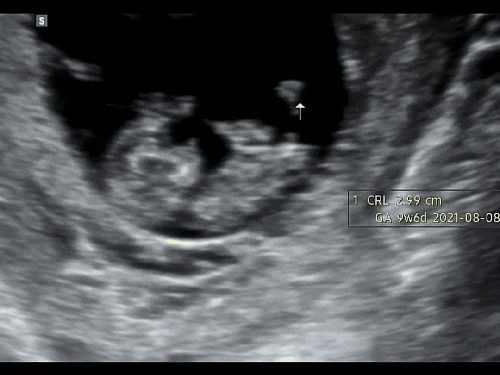

임신 6주-9주 초음파 사진 영상 이에요~

안녕하세요~ 임신 6주차 기록을 이제 남겨요~ 6주부터 본격적인 입덧으로 입덧 캔디와 새콤달콤을 달고 살...